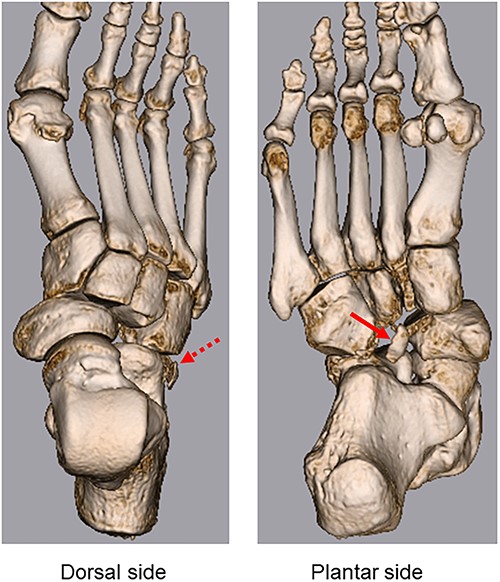

A 57-year-old carpenter fell from a height of 6 m and hit the right half of his body. He visited the emergency department of our hospital the same day. Physical examination revealed tenderness, swelling and deformity in the right foot (Fig. 1). Plain radiography, computed tomography (CT) and three-dimensional (3D) CT showed an uncommon injury; lateral dislocation of the naviculocuneiform joint, lateral dislocation of the calcaneocuboid joint, compression fracture of the calcaneus and avulsion fracture of the cuboid in the right foot (Figs 2 and 3). The next day, we attempted closed reduction, but the reduction was unstable. Percutaneous fixation with Kirschner wires (K-wires) was performed to stabilize the dislocated fragments. Two 1.5-mm K-wires were inserted from the navicular and cuboid bones to the medial cuneiform and calcaneus bones, respectively, and the dislocated joints were stabilized (Fig. 4). Postoperatively, the foot was immobilized with a below-knee splint. Mild ankle exercise was initiated in the early postoperative phase. The K-wires were removed at 8 weeks. Full weight-bearing was started at 14 weeks, and he was able to walk without pain. At 19 weeks, he returned to his job. At 1 year after the operation, the American Orthopaedic Foot and Ankle Society midfoot score was 75/100 points. He had mild and occasional pain, but he could walk about 2000 steps consecutively with no support or difficulty, and he had no marked limitation of daily activities. Fracture dislocation sites were stable on plain radiography (Fig. 5).

3D CT shows lateral dislocation of the naviculocuneiform and calcaneocuboid joints of the right foot, with fractures of the anterior edge of the calcaneus (broken arrow) and medial edge of the cuboid (arrow).

Midtarsal injuries tend to occur following high-energy trauma, namely, a traffic accident or fall from a height [4]. Previous studies have reported that these injuries were frequently overlooked or misdiagnosed [1]. Midfoot injury can negatively influence social aspects such as work and recreational activities. Therefore, early diagnosis and treatment of these injuries are required to avoid instability, long-term functional problems, foot pain and severe complications. History of the injury and physical examination is important for diagnosis. The most common symptom is severe pain; additionally, foot deformity can be masked by marked localized swelling on physical examination [4]. Since the injury tends to occur as a result of high-energy trauma, damage to other parts of the body should also be considered. In addition to plain radiography, CT is useful in diagnosing injuries; 3D CT provides more detailed images to diagnose small fractures and bone fragments [4]. In the present case, small fractures of the medial edge of the cuboid and anterior edge of the calcaneus were diagnosed using 3D CT (Fig. 3).